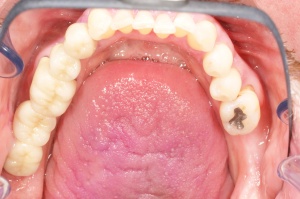

Ab dem Februar 2004 wurde der Patient zur Sicherung des Behandlungserfolges in das in der FU VIIa – Zahnmedizin seit 1996 praktizierte Recallsystem aufgenommen. Diese Erhaltungstherapie beinhaltet die bereits erwähnten Maßnahmen der Unterstützenden Parodontitistherapie (UPT). Aufgrund dienstlicher Erfordernisse (u. a. immer wieder Seefahrten des Patienten) konnte der zunächst geplante Abstand von vier Monaten nicht immer eingehalten werden. Ein Abstand von ca. sechs Monaten konnte jedoch trotz der teilweise schwierigen Rahmenbedingungen realisiert werden. Am Zahn 44 kam es im Jahr 2006 zu einem Rezidiv, sodass an diesem Zahn im September 2006 eine Lappenoperation durchgeführt wurde. Der intraoperativ vorgefundene tiefe cirkuläre vertikale Defekt führte zur Einschätzung einer langfristig fraglichen Prognose von 44. Im Zuge der weiteren Erhaltungstherapie zeigten sich bis auf 44 die parodontalen und periimplantären Gewebe völlig unauffällig: So betrugen die Sondiertiefen bei entzündungsfreien klinischen Verhältnissen durchweg zwei bis drei Millimeter. Auch radiologisch zeigten sich keine Auffälligkeiten. Es gab keine Progredienz der ehemaligen parodontalen Erkrankung, die Osseointegration der Implantate zeigte keine Veränderungen (s. Abb. 7). Erhöhte Sondiertiefen verblieben lediglich am Zahn 44. Nachdem sich trotz regelmäßiger Nachsorge an 44 keine Entzündungsfreiheit der marginalen Gingiva erzielen ließ und die Zahnlockerung von 44 zunehmend stärker wurde, erfolgte im Jahre 2010 die Entfernung des Zahnes und der Ersatz durch eine implantatgetragene Krone (s. Abb. 8). Die Erhaltungstherapie wurde fortgeführt, Behandlungsmaßnahmen über die Inhalte der UPT hinaus waren bis zur Entlassung des Soldaten im Jahre 2012 nicht erforderlich. Der Patient blieb jedoch auch nach der Entlassung aus dem aktiven Dienst Patient des Hauses, sodass die Erhaltungstherapie in der FU VIIa – Zahnmedizin fortgeführt werden konnte. Im April 2013 stellte sich der Patient mit Beschwerden am Zahn 45 vor, der Zahn wies zudem eine Lockerung des Grades II auf. Die durchgeführte Röntgendiagnostik (s. Abb. 9) zeigte eine Wurzelfraktur im apikalen Wurzeldrittel, ein Zahnerhalt von 45 war nicht möglich und der Zahn wurde noch in gleicher Sitzung entfernt. Zur Versorgung der Lücke wären verschiedene prothetische Lösungen möglich gewesen. Letztlich fiel die Entscheidung zugunsten eine Extensionsbrücke von regio 45 auf 48. So konnte die Implantatkrone 44 belassen und mit dem Lückenschluss mittels einer vergleichsweise einfachen und schnellen prothetischen Versorgung auch die Schaltlücke 46 geschlossen werden. Der Patient befindet sich nach wie vor in der FU VIIa in der Erhaltungstherapie, die Fotos zeigen den aktuellen klinischen Befund in der Aufsicht des Ober- und Unterkiefers (s. Abb. 10, 11).